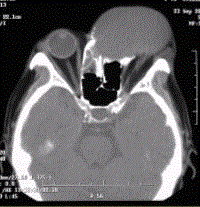

问题 患者男,60岁,头痛,前额部局部隆起。查体:前额隆起处可触及乒乓球样肿块,CT显示如下图。 黏液囊肿的影像学表现,正确的表述有

选项 A.CT表现为鼻窦腔内均匀的浑浊密度影 B.病变边界清楚,窦壁骨质受压变薄,并可见骨质侵蚀 C.MR表现为短T1、长T2信号影 D.MR表现为长T1、长T2信号影 E.病变可累及邻近的眼眶 F.邻近视神经可受压移位 G.MR表现为长T1、短T2信号影

答案 ABCEF

解析 ABCEF